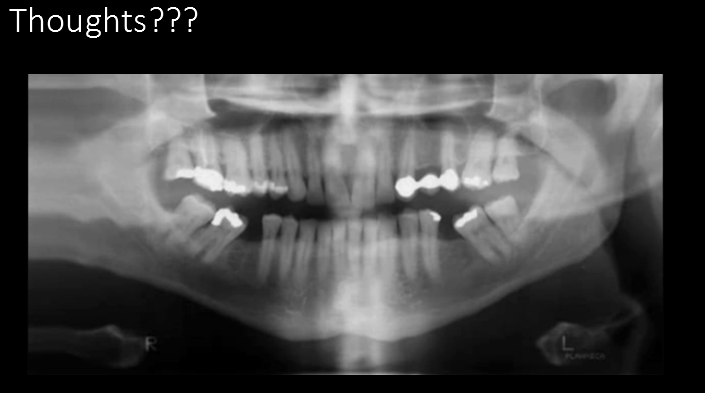

Pano. hit shoulder and dragged

Must check for shoulder clearance; walk around the patient, look from each side.